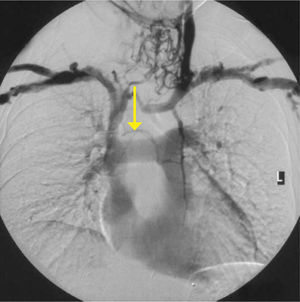

Esto se puede presentar como una imposibilidad de pasar la guía de alambre o un catéter a través del vaso. La presencia de circulación venosa colateral evidente en la pared del tórax, dificultad de compresión venosa con el transductor de ultrasonido o una presión intravenosa elevada al momento de la canulación sugieren este problema. Su confirmación se realiza con venografía, TAC o estudios de ultrasoniodo con doppler (Figura 7). Desplazamientos del mediastino por derrames, colapso pulmonar o neumonectomías movilizará también otras estructuras, incluyendo la VCS. En el caso de oclusión de la VCS, el sistema ácigos aumentara de tamaño para poder aumentar el drenaje venoso.

Sitio de accesoAlgunos estudios sugieren que los catéteres insertados por el lado derecho poseen riesgos menores de trombosis debido a que es una ruta más directa a la vena cava superior, lo que deriva en un más fácil posicionamiento del extremo del catéter. El sitio de inserción depende de factores de los pacientes, accesos a la vena utilizados con anterioridad, experiencia clínica, evidencia de trombosis venosa, cicatrices previas o existencia de colaterales venosos. En casos complicados, es útil recurrir a imágenes de venas centrales (venografía, tomografía computacional, resonancia magnética).